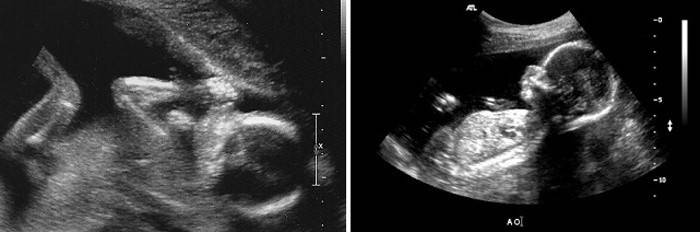

USG

W okresie od 18 do 22 tygodni kobietom w ciąży wyznacza się drugie zaplanowane badanie ultrasonograficzne w celu ustalenia płci dziecka, a także badania głównych wskaźników odzwierciedlających wzrost i rozwój dziecka. Niniejsze badanie ma na celu identyfikację wad rozwoju płodu i rażących wad rozwojowych narządów wewnętrznych. lekarz dokładnie bada serce i nerki płodu pod kątem ich nieprawidłowości, może ustalić rzekome objawy zespołu Downa lub rażące wady mózgu.

Ponadto za pomocą ultradźwięków płodu odbywa się szczegółowy skan łożyska, oceniana jest jego struktura i pępowina z naczyniami, oceniane są główne wskaźniki:

- obwód brzucha i głowy płodu,

- rozmiar potyliczno-czołowy

- wymiary rurkowych kości uda, dolnej części nogi, barku i przedramienia.

Możliwe jest również przeprowadzenie USG 3D ze zdjęciami lub nagrywanie dziecka na karcie flash.